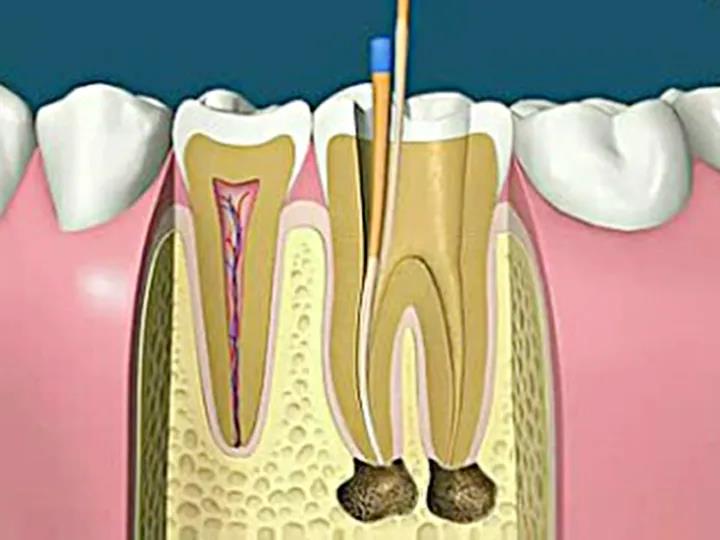

根管治疗切断牙神经

3d视频演示牙齿神经去除牙齿的根管治疗过程